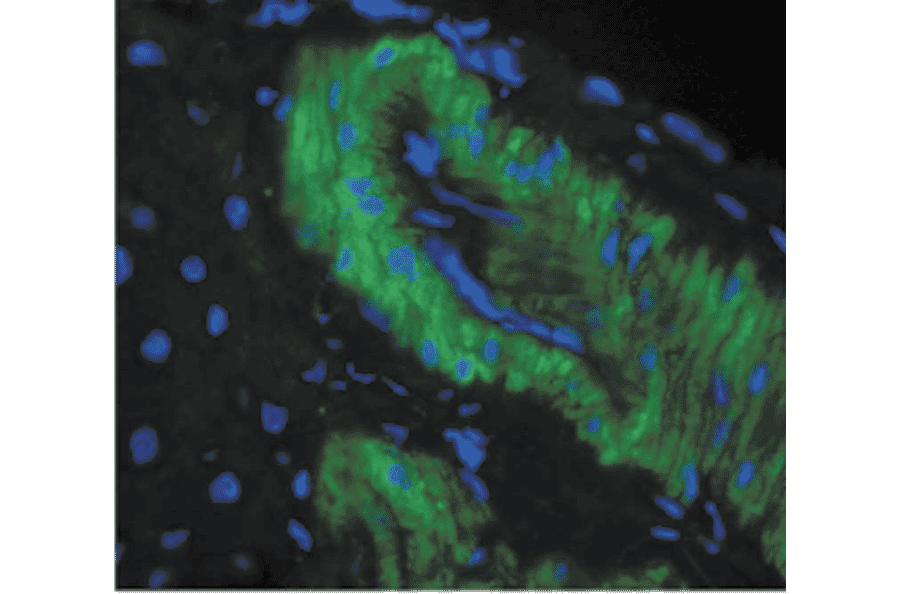

Immunohistochemistry analysis of rat liver tissue. The Primary Antibody used was Anti-Nitrotyrosine Antibody [39B6] (A304794) at 1:1,000. The secondary antibody used was FITC Goat Anti-Mouse (green).